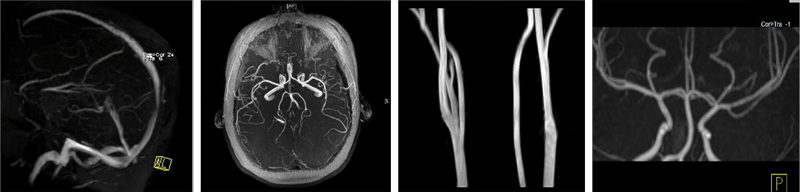

Examples

- Image 1 – Here we have a 2D TOF sequence of the venous system of the brain. Arterial flow has been suppressed by placing a pre-sat band below the brain because arterial flow comes from below

- Image 2 – This image is a 2D TOF of the arterial system of the brain. To suppress venous flow, we place the saturation band above the brain

- Image 3 – This image is a 3D TOF of the carotid arteries in the neck

- Image 4 – The last image is a coronal 3D TOF of the cerebral arteries in the coronal plane